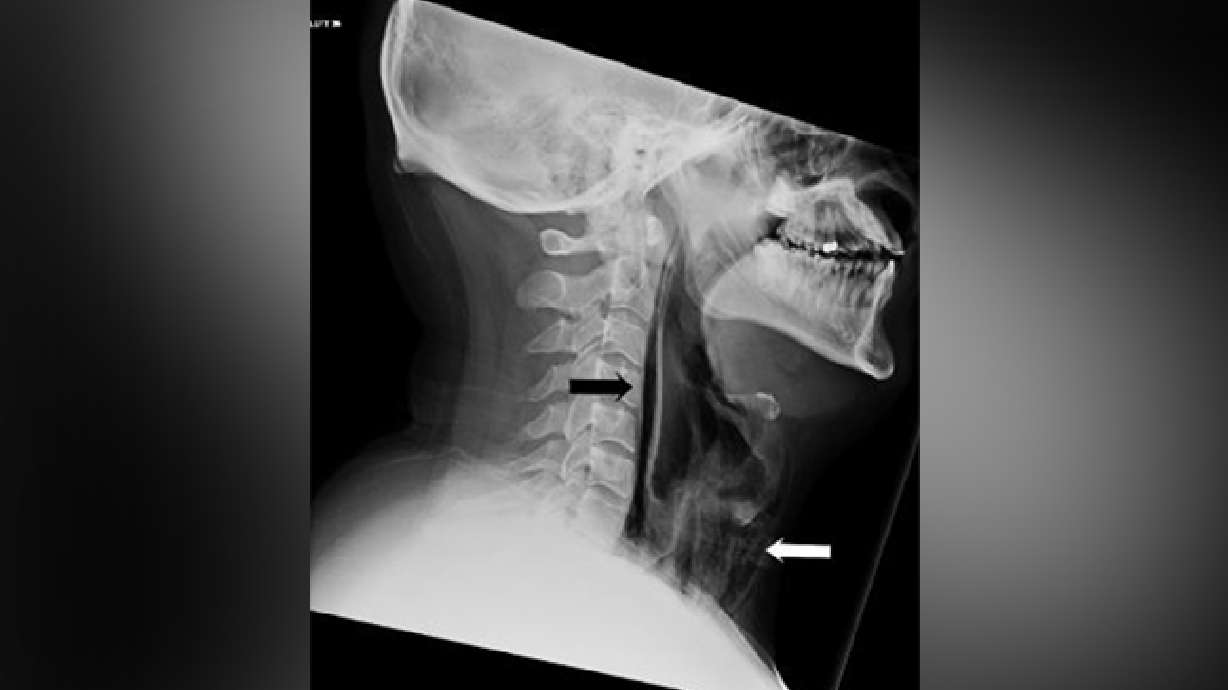

Scans confirmed the problem. The tests showed actual streaks of air in the retropharyngeal region and extensive surgical emphysema in the neck anterior to the trachea. In other words, by trying to hold in his sneeze, he actually blew a small hole in his throat.